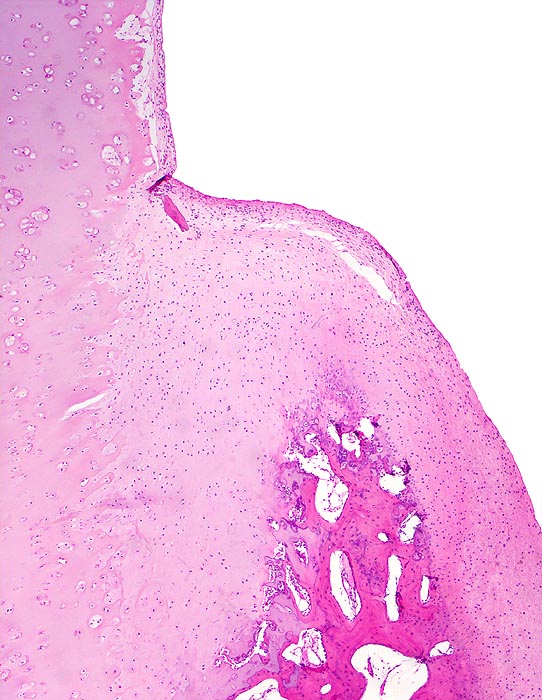

• Deformierte Gelenkfläche.

• Weitgehendes Fehlen des hyalinen Gelenkknorpels.

• Sekundäre Sklerose der freiliegenden Spongiosa mit Anbau von breiten Faser- und Lamellenknochensäumen an die alten Bälkchen.

• Leichte Osteoporose in der craniolateralen Entlastungszone.

• Herde von metaplastischem Faserknorpel in der Gelenkfläche.

• Randosteophyt, welcher über Resten des dort noch vorhandenen Gelenkknorpels entstanden ist (Verdoppelung des Knorpels).

• Nekrosebezirk in der Spongiosa (Geröllzyste) umgeben von einem Granulationsgewebssaum und Narbengewebe.